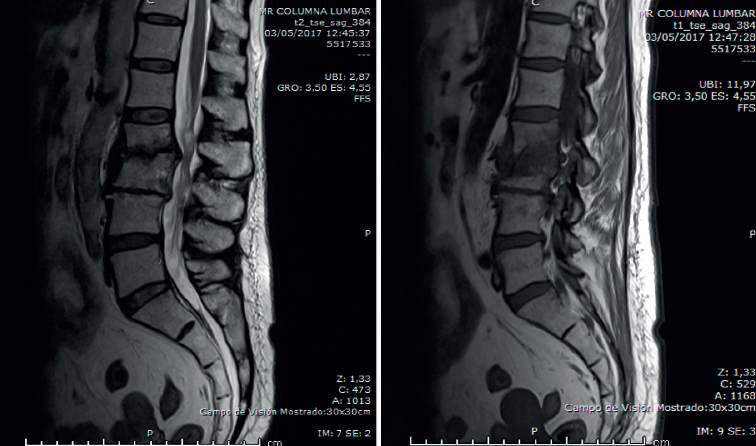

Figura 1. Radiografías de frente y de perfil lumbares.

• La radiología simple lumbar (Figura 1) de frente y de perfil muestra grave discopatía L2/L3 con práctica desaparición del disco intervertebral.